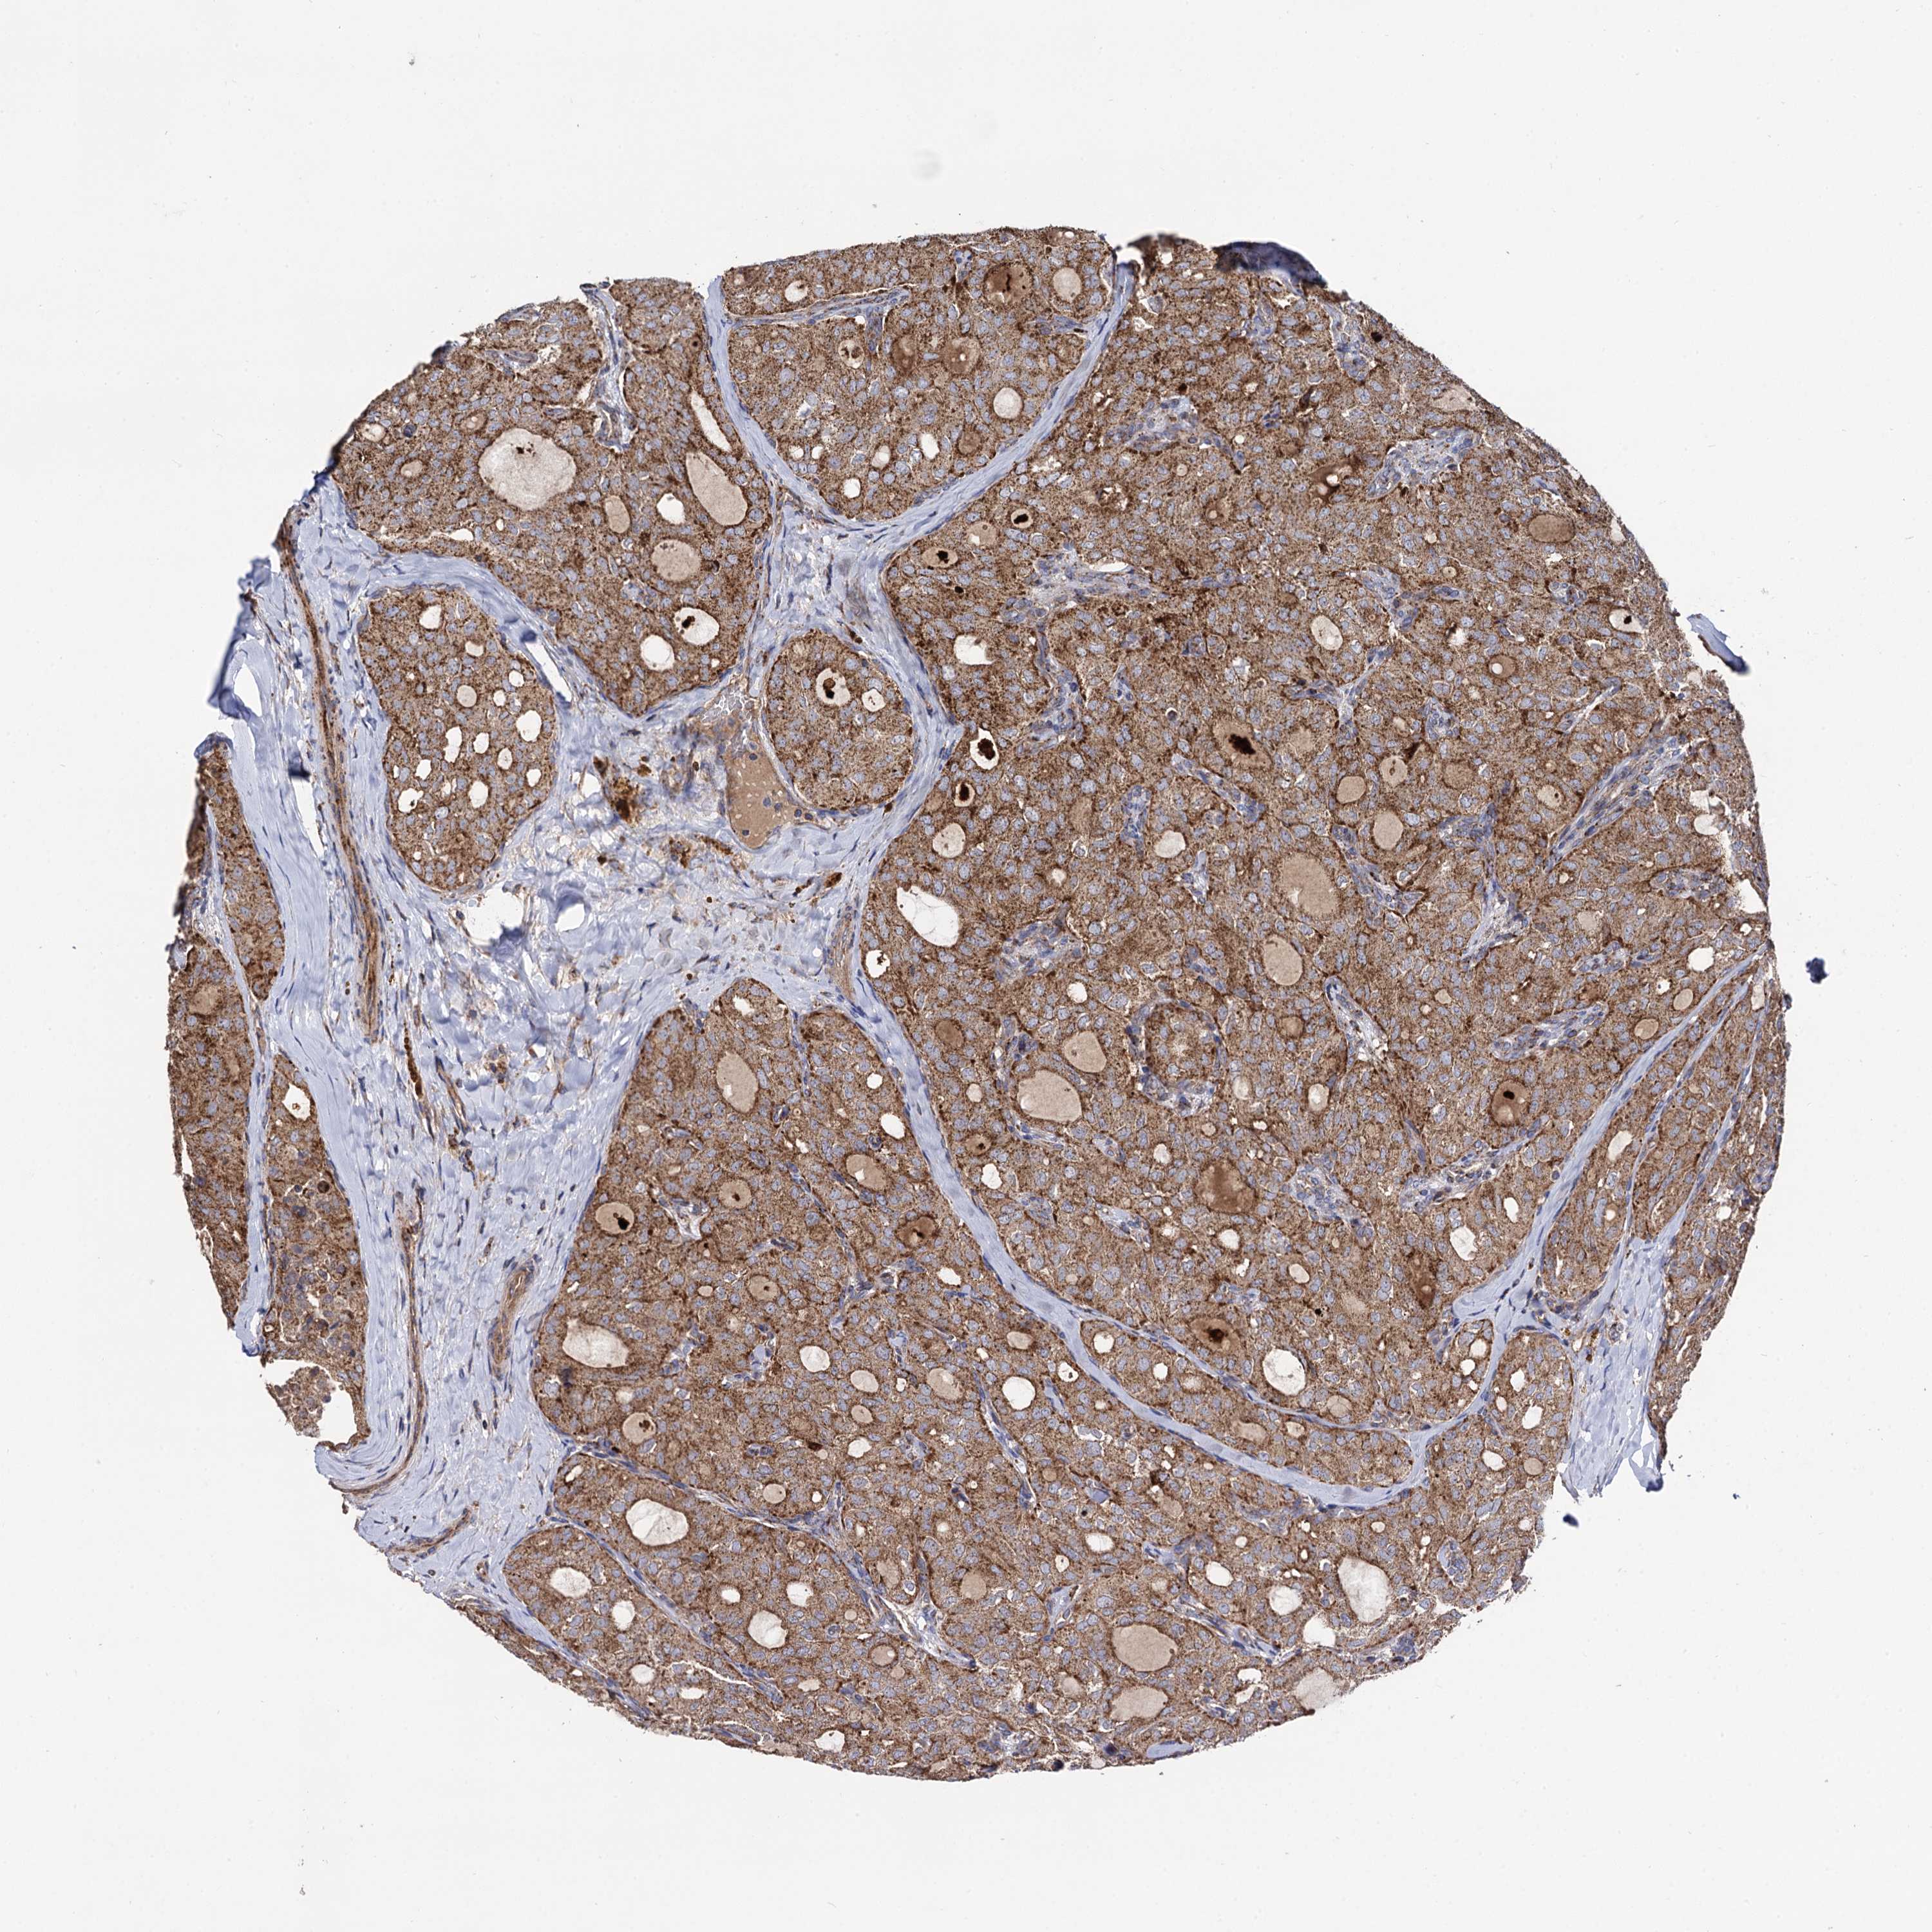

THYROID CANCER - Protein expressioni

A mouse-over function shows sample information and annotation data. Click on an image to view it in a full screen mode. Samples can be filtered based on level of antibody staining by selecting one or several of the following categories: high, medium, low and not detected. The assay and annotation is described here.

Note that samples used for immunohistochemistry by the Human Protein Atlas do not correspond to samples in the TCGA dataset.

Antibody stainingi

Antibody staining in the annotated cell types in the current human tissue is reported as not detected, low, medium, or high, based on conventional immunohistochemistry profiling in selected tissues. This score is based on the combination of the staining intensity and fraction of stained cells.

Each image is clickable and will lead to virtual microscopy that enables deeper exploration of all samples and also displays staining intensity scores, fraction scores and subcellular localization as well as patient and tissue information for each sample.

Antibody HPA040845

Staining

High

Medium

Low

Not detected

Intensity

Strong

Moderate

Weak

Negative

Quantity

>75%

75%-25%

<25%

None

Location

Nuclear

Cytoplasmic/membranous

Cytoplasmic/membranous,nuclear

Papillary adenocarcinoma, NOS

Follicular adenoma carcinoma, NOS